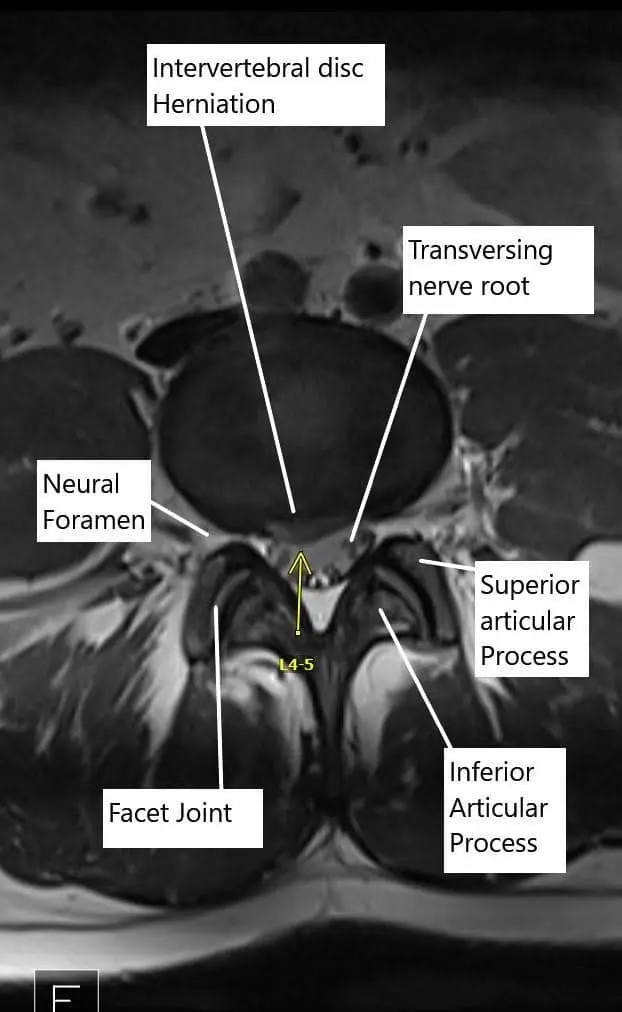

Axial section of the Lumbosacral MRI at L4-L5 level.